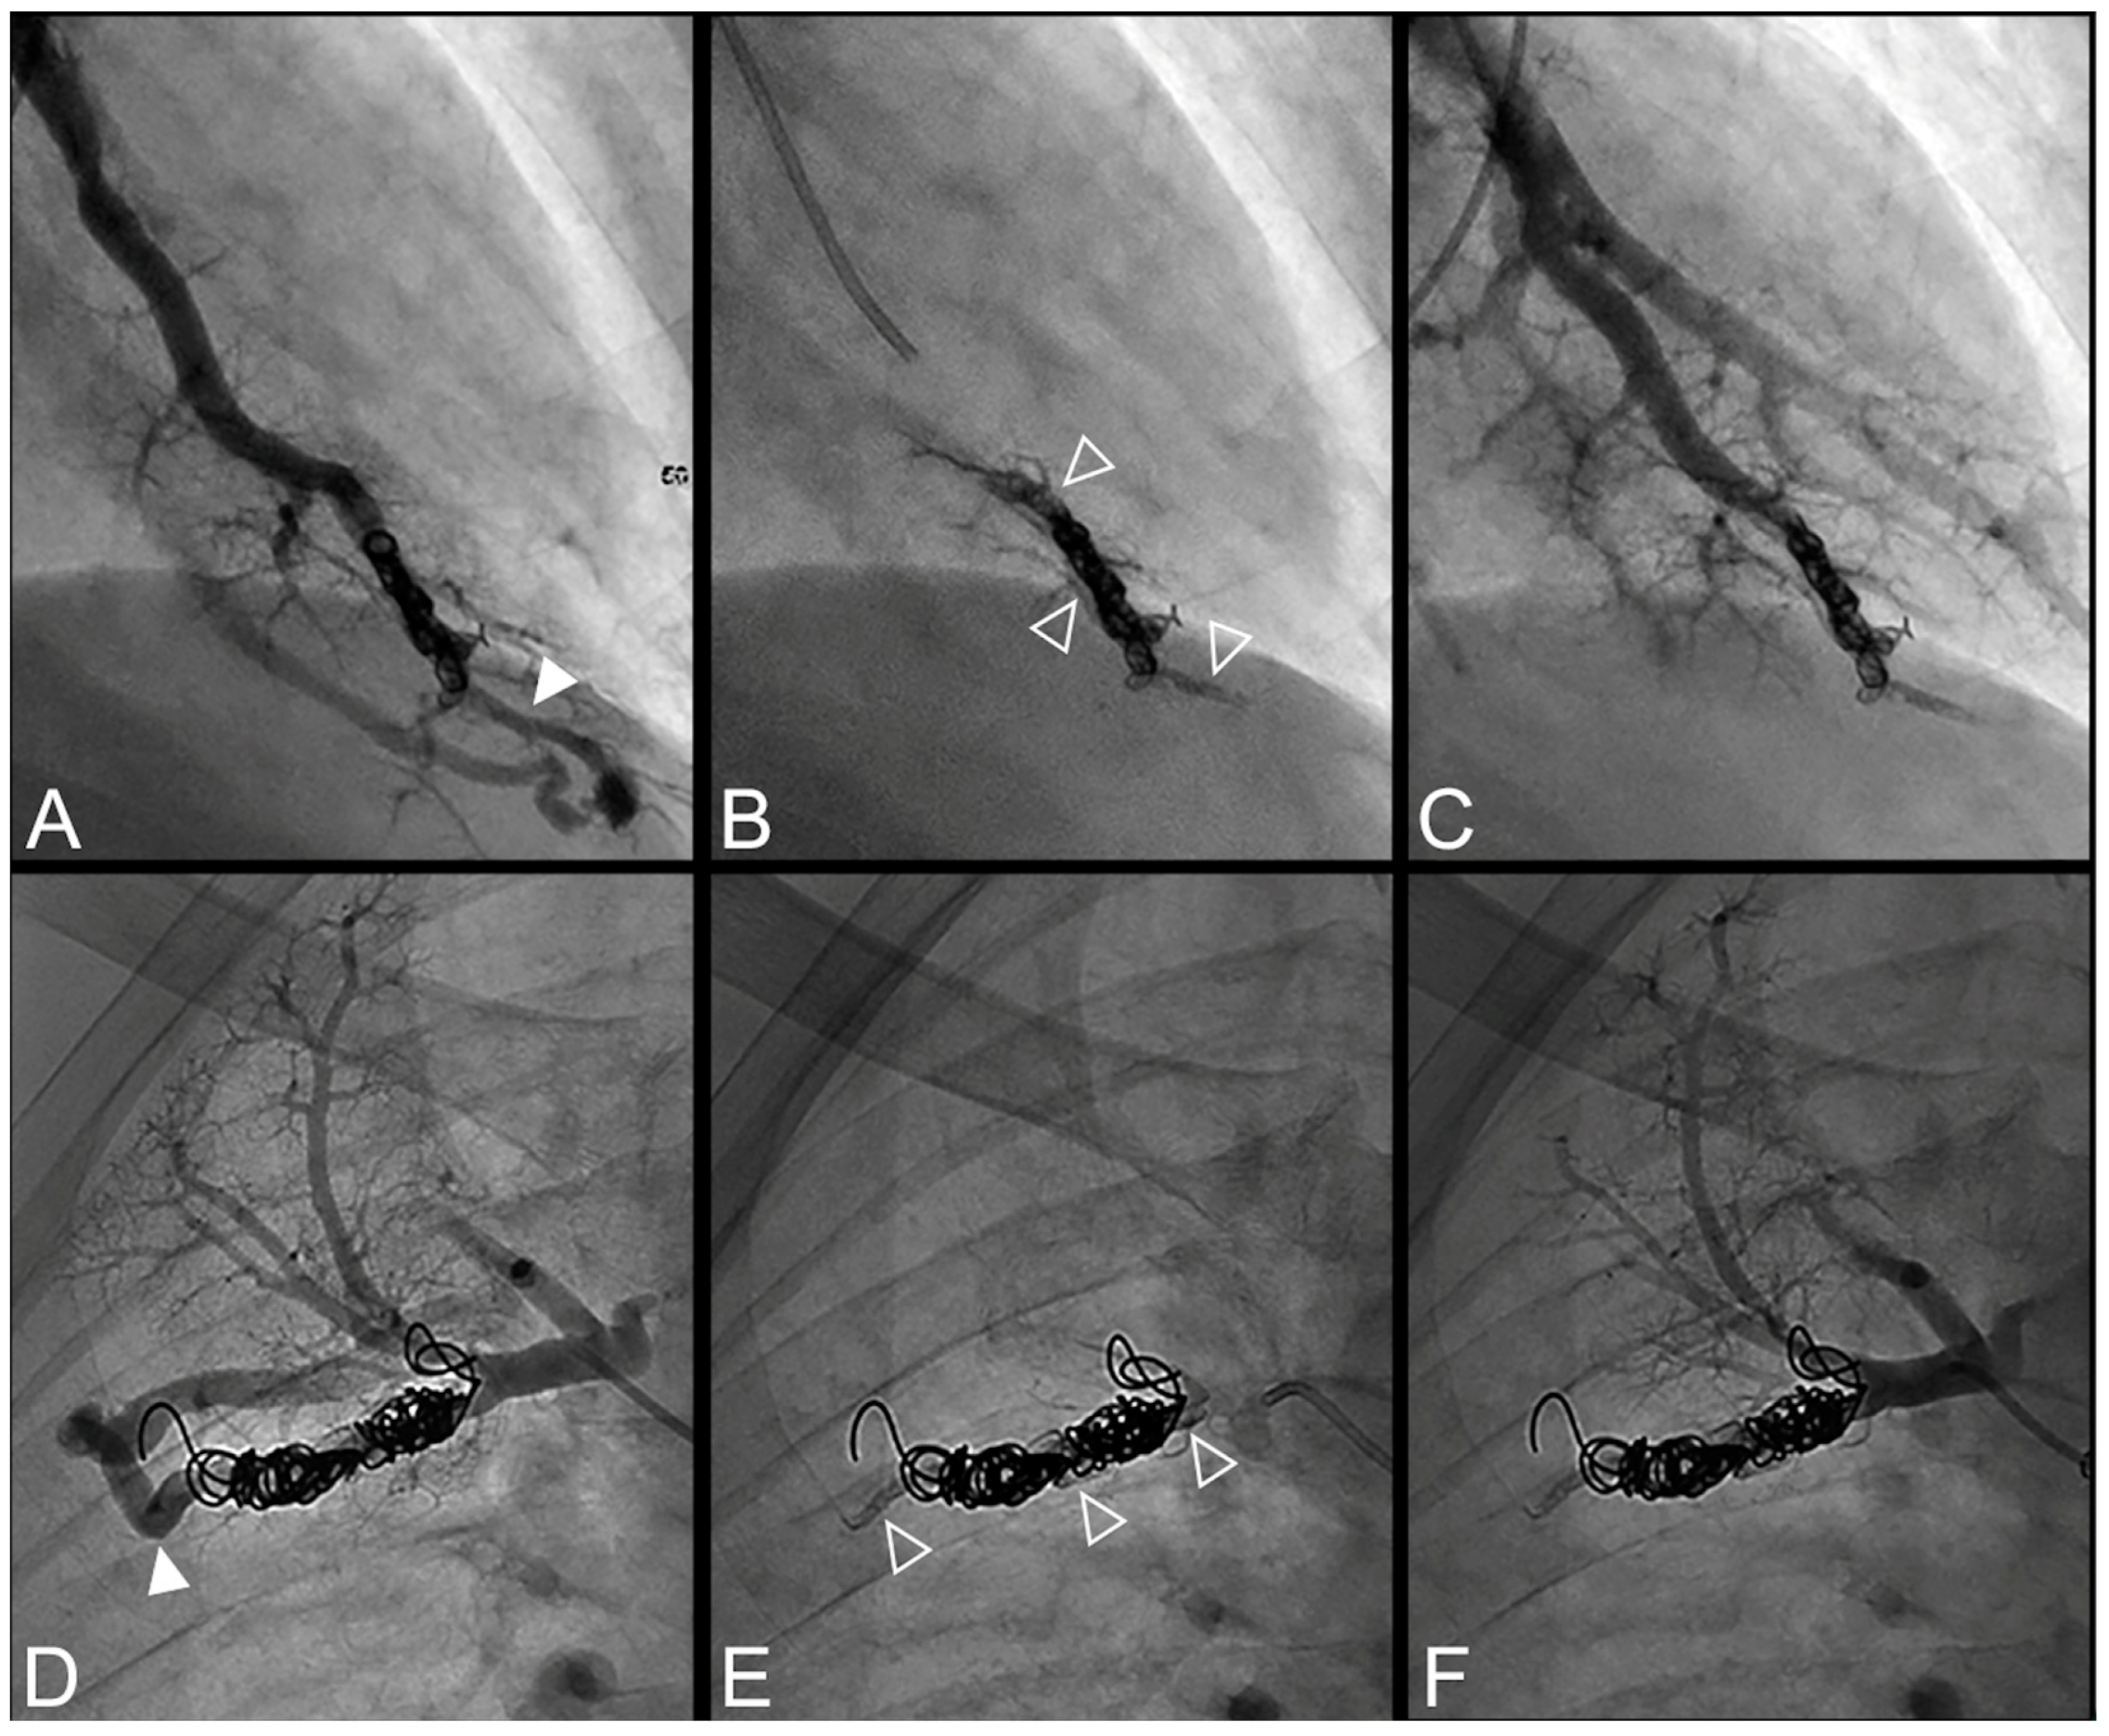

Figure 2.

Case examples of a 68-year-old man (A–C) and 48-year-old man (D–F) treated for a simple recurrent pulmonary arteriovenous malformation. In both cases, digital subtraction angiography unsubtracted images showed a distance >10 mm between the first coil and the aneurysmal sac, which is considered a risk factor for recanalization. (A–C). Embolization was performed using Onyx® (0.3 mL) to fill the afferent artery in and downstream of the pre-implanted coils and resulted in an immediate complete occlusion, maintained after 23 months follow-up. No leak in the aneurysm or in the vein was reported. (A). Opacification of the afferent artery showed a recanalization through the pre-implanted coils (full arrowhead). (B). Opacity within, downstream and upstream of the coils (empty arrowheads) showed the distribution of Onyx® without any evidence of a leak in the aneurysmal sac. (C). Opacification of the afferent artery showed the absence of opacification of the aneurysmal sac and the efferent vein in favor of immediate occlusion. The opacification of the healthy arterial branch did not reveal any perfusion defect. (D–F). Embolization was performed using Onyx® (0.4 mL) to fill the afferent artery in and downstream of the pre-implanted coils and resulted in an immediate complete occlusion, with a recurrence 36 months after the procedure. No leak in the aneurysm or in the vein was reported. (D). Opacification of the afferent artery showed a recanalization through the pre-implanted coils (full arrowhead). (E). Opacity within, downstream and upstream of the coils (empty arrowheads) showed the distribution of Onyx® without any evidence of a leak in the aneurysmal sac. (F). Opacification of the afferent artery showed the absence of opacification of the aneurysmal sac and the efferent vein in favor of immediate occlusion.